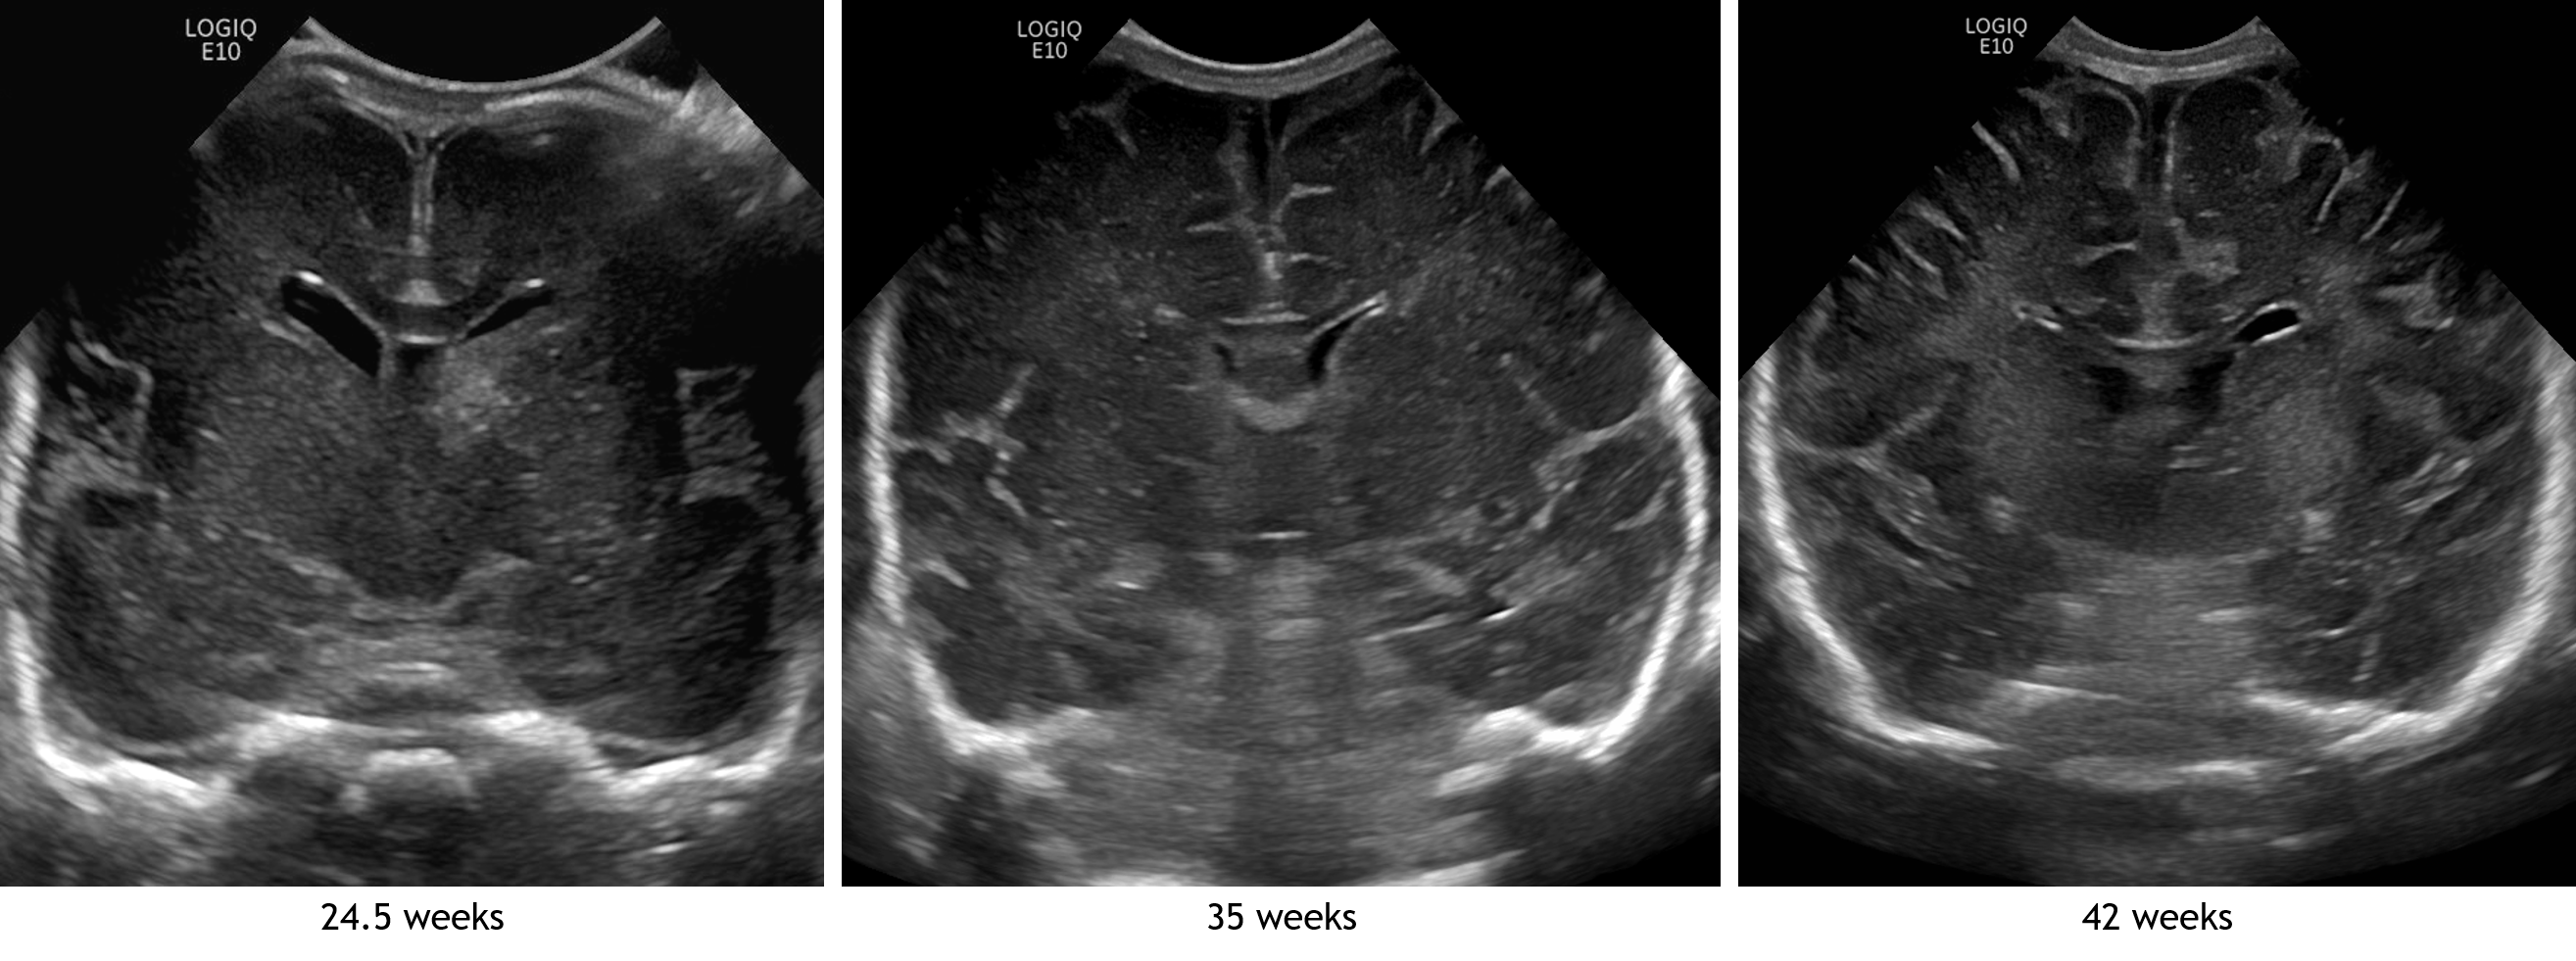

Age: 4 days (born at 24 weeks)

Sex: Male

Indication: Evaluate for germinal matrix hemorrhage

Grade 2 germinal matrix hemorrhage

Sample ReportLeft germinal matrix hemorrhage involving the caudothalamic groove and layering in the occipital horn of the left lateral ventricle without hydrocephalus (grade 2).

No abnormal brain parenchymal echogenicity or extra-axial collections.

Premature sulcation pattern.

| Grade | Hemorrhage location | Hydrocephalus |

|---|---|---|

| 1 | Confined to caudothalamic groove | Absent |

| 2 | Intraventricular hemorrhage | Absent |

| 3 | Intraventricular hemorrhage | Present |

| 4 | Intraparenchymal hemorrhage | Absent/Present |